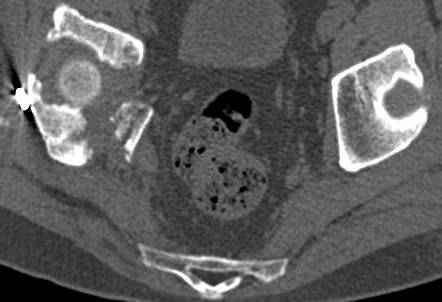

Интересно было бы посмотреть рентгенограммы до операции. У меня впечатление, что я не все вижу, что тут есть... Уважаемые Господа "тазисты" и "тазологи", к какому типу переломов вертлужной впадины по Летурнелю вы бы отнесли это случай?

Из переломов проходящих через крыло и/или заднюю стенку ни простой перелом "передней колонны" (явно имеется пером задней стенки, и не видно перелома седалищной или лонной), ни простой "поперечный", ни ассоциированный "Т-образный" (т.к есть перелом крыла и не видно перелома седалишной), ни ассоциированный "задняя колонна+задняя стенка", на ассоциированный "поперечный+задняя стенка", ни ассоциированный "передняя колонна+задняя гемисфера" (не видно перелома седалищной), ни ассоциированный "обе колонны" (не видно перелома лонной седалищной) не подходят под эту классификацию....

к таковым себя не причисляю, но...обычное дело для нашей страны - выкладывать 3D и не показывать стандартные проекции Judet. Дигност представляет те ракурсы, которые по-его мнению наиболее информативны, более того комп сам достраивает какие-то мелкие повреждения по 3D по своему усмотрению. По данной реконструкции можно предполагать высокий двухколонный перелом с оскольчатыми передней и задней колоннами, оскольчатую высокую переднюю колонну с задним полупоперечником или одно из перечисленных с вовлечение КПС. У меня впечатление за второй вариант, но нужно обследовать нормально - проекции, сканы.

высылаю дополнительно сканы.

итак, второй вариант: высокий двухколонный с вовлечением КПС... Ни одно из основных повреждений не репонировано, кроме задней стенки. Скорее всего попытка реконструкции вертлуги сейчас будет очень травматичной и не очень эфективной, т.е. вероятный риск более значим, чем ожидаемая польза... Лучше подождать, и потом сразу эндопротез